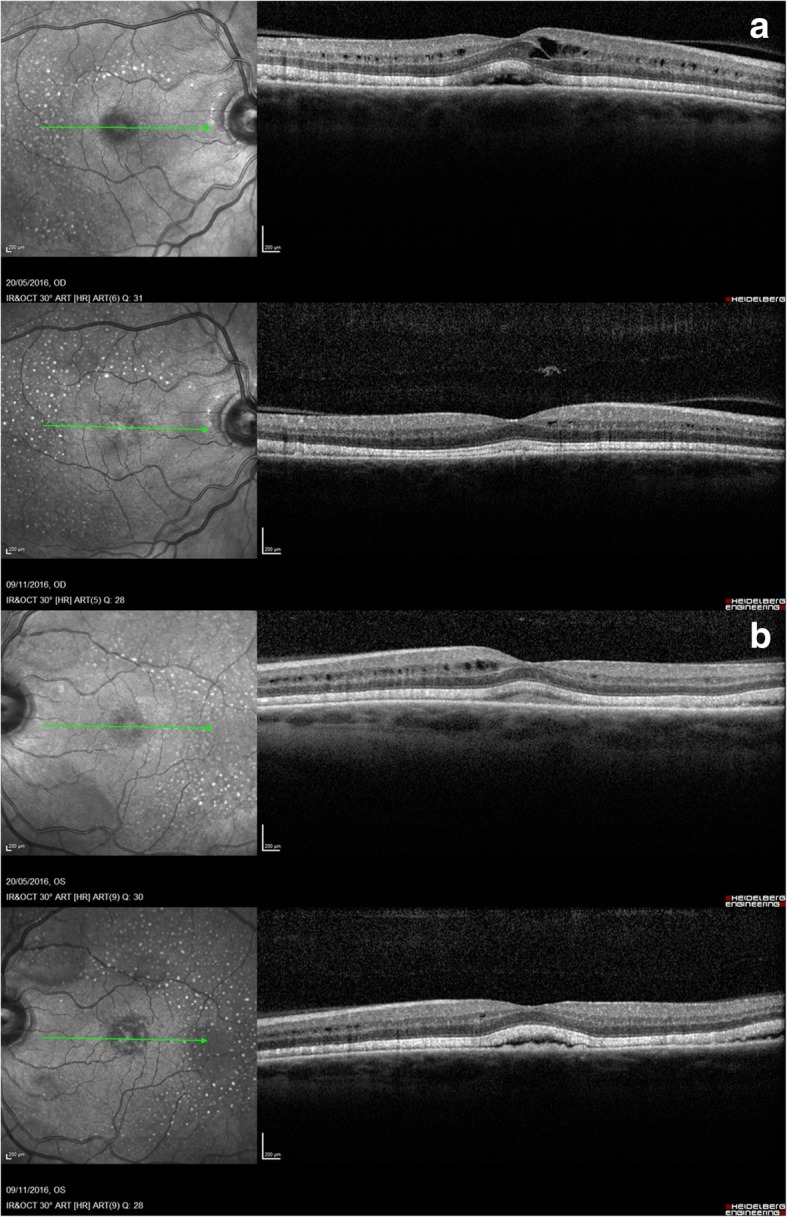

Fig. 3.

OCT images 5 days after stopping treatment: Intra-retinal and sub-retinal fluid, thickening of ellipsoid zone, sub-retinal deposits and multiple hyper-fluorescent spots on IRR image

A 71-year-old presented to community optometrist with ‘patchy vision’ and ‘green circular patches’ in central vision of both eyes for 2–3 weeks. He was noted to have bilateral cystoid macular edema on optical coherence tomography (OCT) scan and was referred to hospital eye services (Fig. 1). The patient had previously received annual ophthalmic assessments and retinal imaging by optometrist which were unremarkable. He had been seen in eye clinic with left sided herpes zoster ophthalmicus disciform keratitis and uveitis 7 months previously with no retinal involvement. His medical history included hypertension and multiple relapsed stage IV BRAF gene mutant malignant melanoma involving skin, liver and spleen for 11 years. The melanoma nodules were present on buttock, back and periumblical region. He had been treated with surgical excision of nodules, inguinal nodal and femoral vein resection and radiotherapy with consequent lymphoedema of lower limb over years. His most recent melanoma relapse was 15 months previously and was treated with 3 cycles of Ipilimumab which were later discontinued due to uncontrolled diarrhoea. Subsequently, he was found to have enlargement of periumbilical and liver melanoma nodules with appearance of a new nodule in the lung. At this point he was commenced on molecularly targeted oral chemotherapeutic agents, Dabrafenib (Tafinlar) 150 mg twice a day (BD) initially followed by Trametinib (Mekinist) 2 mg once a day (OD) for 7 months and 4 months respectively. Since the molecularly targeted therapy is known to have ocular side-effects the patient was given comprehensive side-effect profile information at the initiation of treatment and was advised to seek immediate ophthalmic assessment if any visual disturbance. This prompted him to see his optometrist at the onset of symptoms. In view of the ocular symptoms, the oncology team advised him to stop his chemotherapeutic drugs, Dabrafenib and Trametinib and requested specialist ophthalmology review. He was seen in eye clinic 5 days after stopping treatment. His symptoms were marginally better. The visual acuity was 6/6 in both eyes on Snellen’s chart. The anterior segments were normal. Fundus examination showed healthy optic discs, macula showed dull foveal reflex with normal periphery and retinal vasculature (Fig. 2). The OCT scan showed intra-retinal and sub-retinal fluid on macula with cystoid changes in the peri-foveal area. More strikingly, there was significant thickening of the ellipsoid zone and sub-retinal granular deposits overlying an intact looking retinal pigment epithelium (RPE). Infrared reflectance image (IRR) showed multiple hyper-reflective lesions that corresponded to the sub-retinal granular deposits on OCT imaging. These deposits were distributed in bilateral symmetrical ‘starry sky’ appearance on the macula (Fig. 3). The choroid appeared unaffected with choroidal thickness of 180 μm in right eye and 225 μm in left eye. On autofluorescence (AF) imaging, the macular sub-retinal granular lesions showed increased autofluorescence (Fig. 4). The macular edema looked improved compared to scans sent by community optometrist.